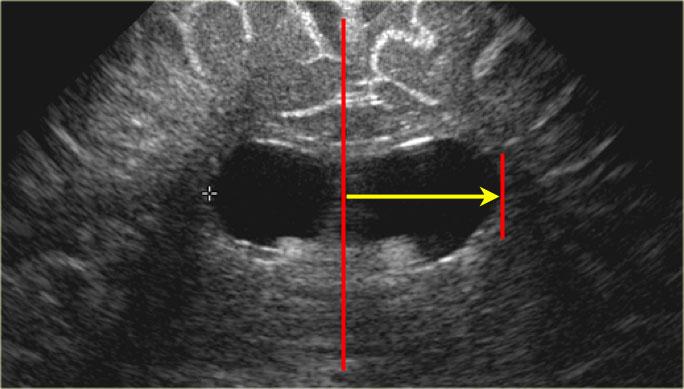

Đo kích thước não thất

Việc đo kích thước hệ thống não thất cần được thực hiện trên một mặt phẳng siêu âm chuẩn, dễ tái lập.

Sử dụng mặt cắt vành (coronal) qua các não thất bên, ở vị trí ngay phía sau lỗ Monro.

Trên mặt cắt này, sẽ thấy 3 chấm tăng âm đại diện cho đám rối mạch mạc trong các não thất bên và ở trần não thất ba.

Ngoài ra, cần thấy được hình ảnh đối xứng của rãnh Sylvius ở cả hai bên và hồi hải mã (mũi tên màu xanh lá và màu cam).

Chỉ số Levene

Đối với tuổi thai đến 40 tuần, nên sử dụng chỉ số Levene; sau 40 tuần, sử dụng chỉ số não thất.

Chỉ số Levene là khoảng cách tuyệt đối từ liềm đại não đến thành ngoài của sừng trán trên mặt phẳng vành, tại mức ngang não thất ba.

Phép đo này được thực hiện cho cả bên trái và bên phải.

Các số đo này có thể được đối chiếu với đường cong tham chiếu và rất hữu ích cho việc theo dõi tiếp theo.